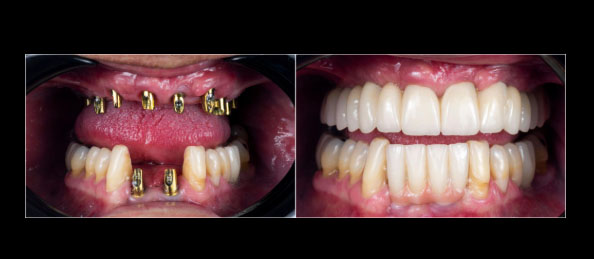

Full Mouth Restoration Case Study Philippines

For patients with severely damaged or missing teeth, full mouth restoration is often required. This includes rebuilding both function and aesthetics.

Treatment Includes:

Tooth extraction (if necessary)

Dental implants or bridges

Zirconia crowns or full-arch prosthesis

Outcome:

Complete smile transformation

Restored chewing ability

Long-term structural stability

Price Comparison:

USA: $25,000 – $60,000

Philippines: $8,000 – $20,000